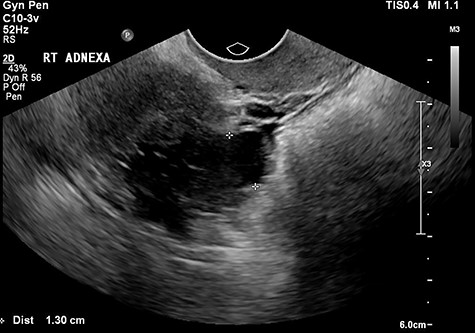

The tertiary ultrasound of the right adnexa demonstrating the 33 mm × 18 mm × 34 mm serpiginous cystic structure with a 13-mm lumen consistent with a hydrosalpinx.

The tertiary level gynaecological ultrasound demonstrated a right adnexal serpiginous structure with a lumen and incomplete septae and a left adnexal cystic structure (Figs 1 and 2). The ultrasonographic features were consistent with those of hydrosalpinges [12]. The Ca125 remained negative. In view of the ultrasound diagnosis of hydrosalpinges and the patient’s post-menopausal status, a laparoscopic BSO was recommended and the patient subsequently consented.